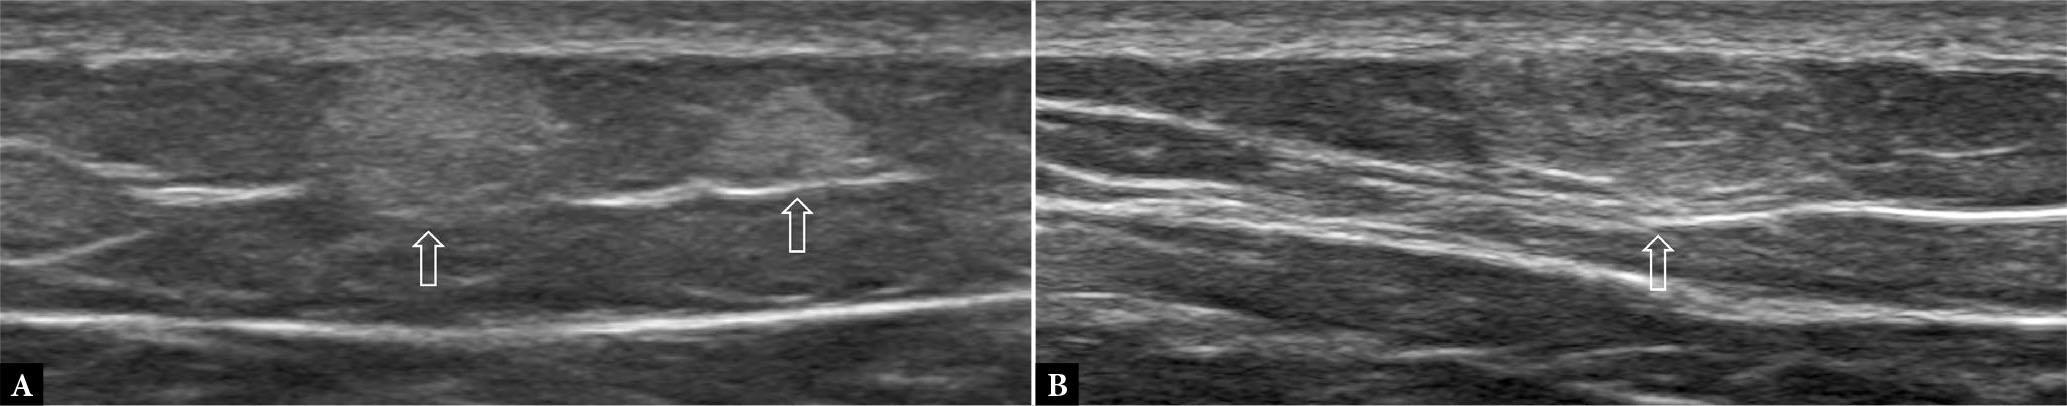

Fig. 5.

44-year-old male with back lump clinically suggestive of lipoma. A., B. Transverse US shows a well-defined, oval-shaped, mildly compressible, mass (open arrow) with thin linear internal striations paralleling long axis of tumor. There was no demonstrable internal vascularity. The appearances are compatible with a subcutaneous lipoma. In this instance, as the tumor lies close to the investing fascia, the tumor margins (arrow) should be checked to confirm that the tumor is superficial to, rather than just deep to, the investing fascia (arrowheads). Subfascial lipomas have a higher risk of malignancy and, therefore, tend to be monitored and treated more actively than subcutaneous lipomas. An atypical lipoma would show features that look for the most part like a lipoma, though it has areas where the fine linear striations may not be readily apparent, and may have areas of calcification or areas of hyperemia